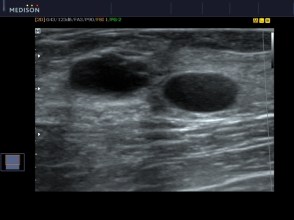

- Less radiation to younger patients because they are of childbearing age. Ultrasound is the modality of choice which will detect any cystic or solid masses in the breast.

This reasoning is far from the truth. A patient maybe called back for simple reasons such as verifying cystic verses a solid mass via ultrasound; to take a more focus view of a lesion or to do a biopsy of a lesion.